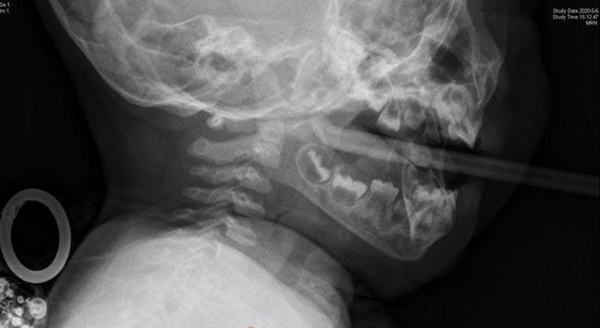

Khi đến được bệnh viện tuyến trên thì bé trai đã có hiện tượng môi tím tái và có nguy cơ ngạt thở. Qua ảnh chụp X-quang cho thấy chiếc que nhỏ đã cắm thẳng vào vòm họng của đứa trẻ, dù phần trước của que rất cùn, không phải là vật sắc nhọn. Sau khi hội chẩn, các bác sĩ quyết định sử dụng phương pháp nội soi gắp dị vật và gây mê toàn thân.

Hỉnh ảnh X-quang và dị vật sau khi được gắp ra khỏi vòm họng bé trai.

Chiếc que nhỏ được gắp ra khỏi họng của cậu bé dài đến 17 cm. May mắn sau đó sức khỏe của cậu bé phục hồi tốt và sớm được xuất viện.